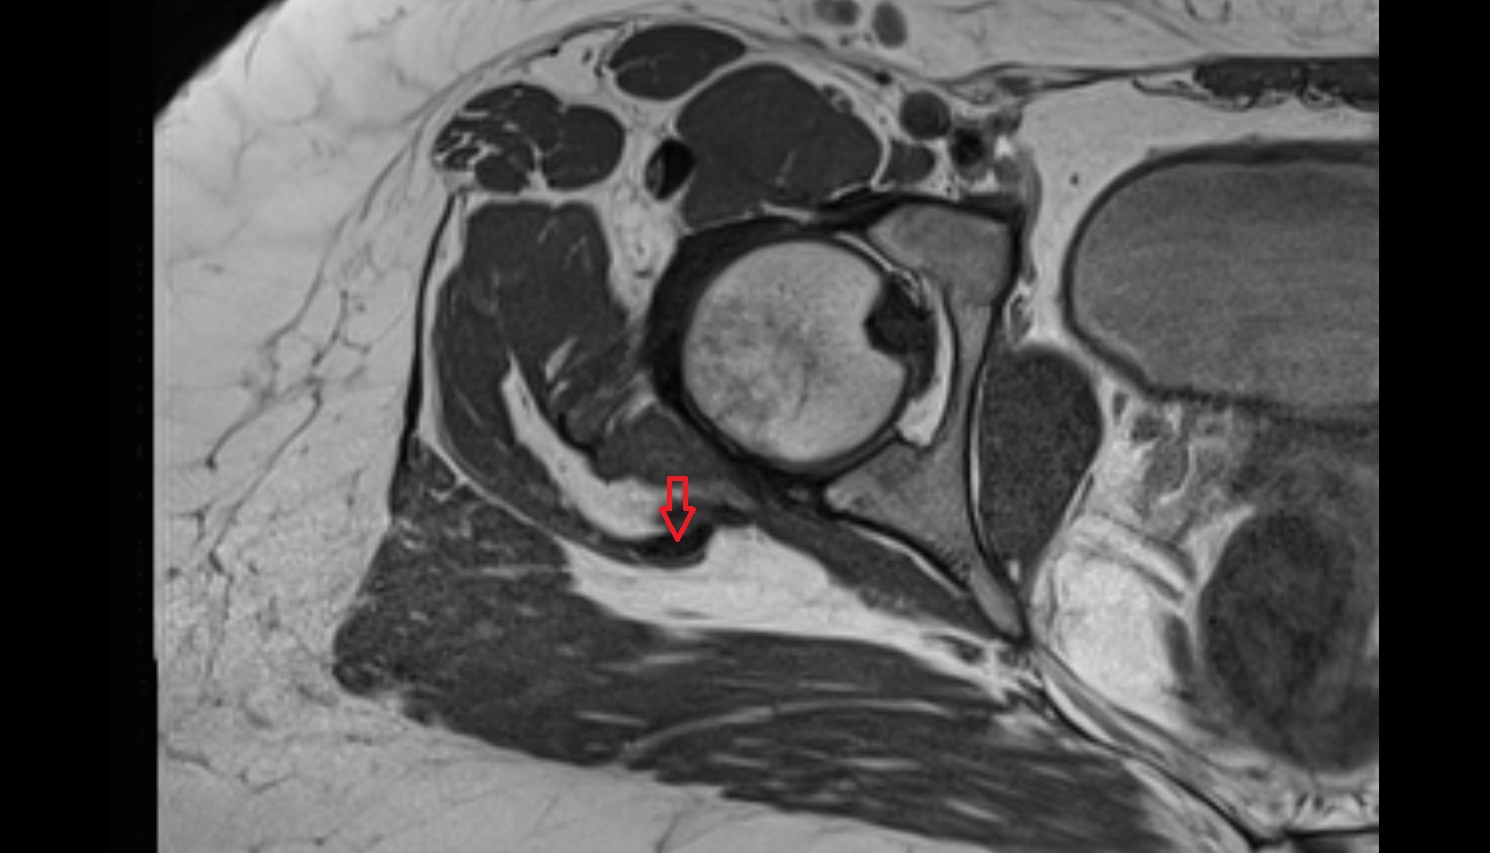

- Peripheral zone of prostate

- Anterior Fibromuscular Stroma of prostate

- Central zone of prostate

- Transitional zone of prostate